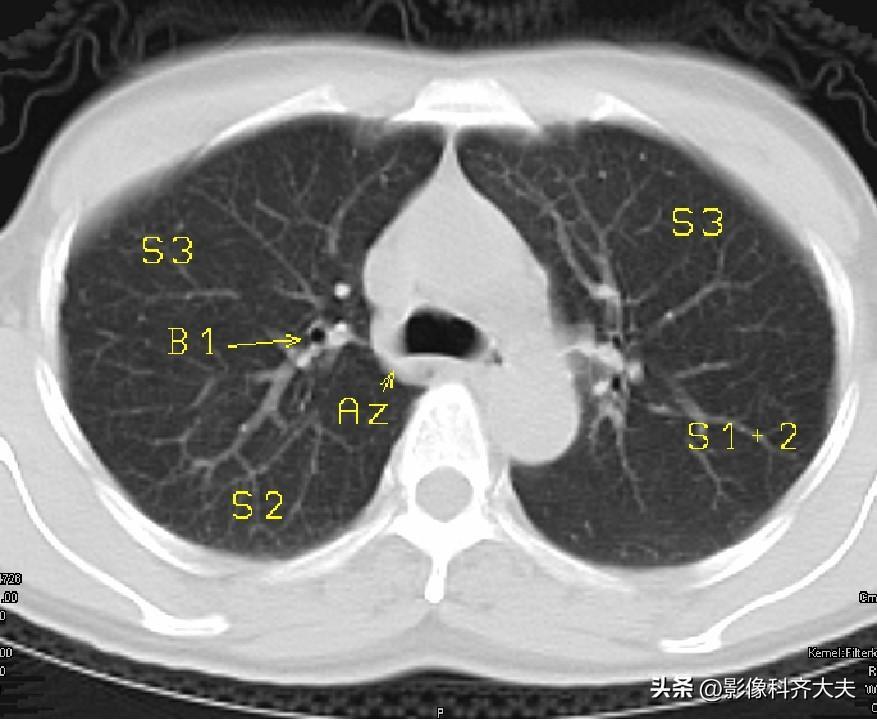

图3-主肺动脉窗层面

▲Az:奇静脉弓,B1:上叶尖段支气管,S3:上叶前段